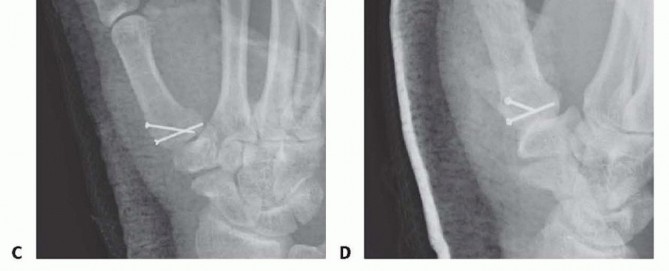

Closed Reduction and Percutaneous Pinning (CRPP)

CRPP is the treatment of choice for classic Bennett fractures where the volar-ulnar fragment is too small to reliably accept a lag screw, yet the joint can be anatomically reduced closed. The reduction maneuver is highly specific, designed to counteract the deforming forces of the APL and Adductor Pollicis. Longitudinal traction is applied to the thumb, followed by palmar abduction and pronation. Direct pressure is then applied to the dorsal-radial aspect of the metacarpal base, effectively pushing the shaft back into the anatomic cradle of the intact volar-ulnar fragment.

Once anatomic reduction is confirmed via multi-planar fluoroscopy, percutaneous fixation is achieved. Typically, two 0.045-inch or 0.062-inch Kirschner wires are utilized. The first wire is driven from the dorsal-radial aspect of the metacarpal shaft directly into the trapezium, effectively neutralizing the proximal pull of the APL. A second wire is often placed transversely from the first metacarpal shaft into the second metacarpal to control rotation and maintain the web space. Pins are cut outside the skin and capped to facilitate easy removal in the clinic.